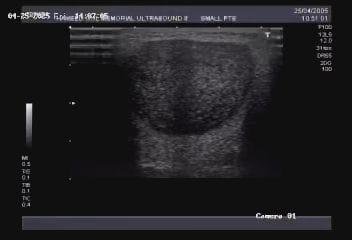

This includes scanning of breast, thyroid, testes, parotid and sub-mandibular glands.